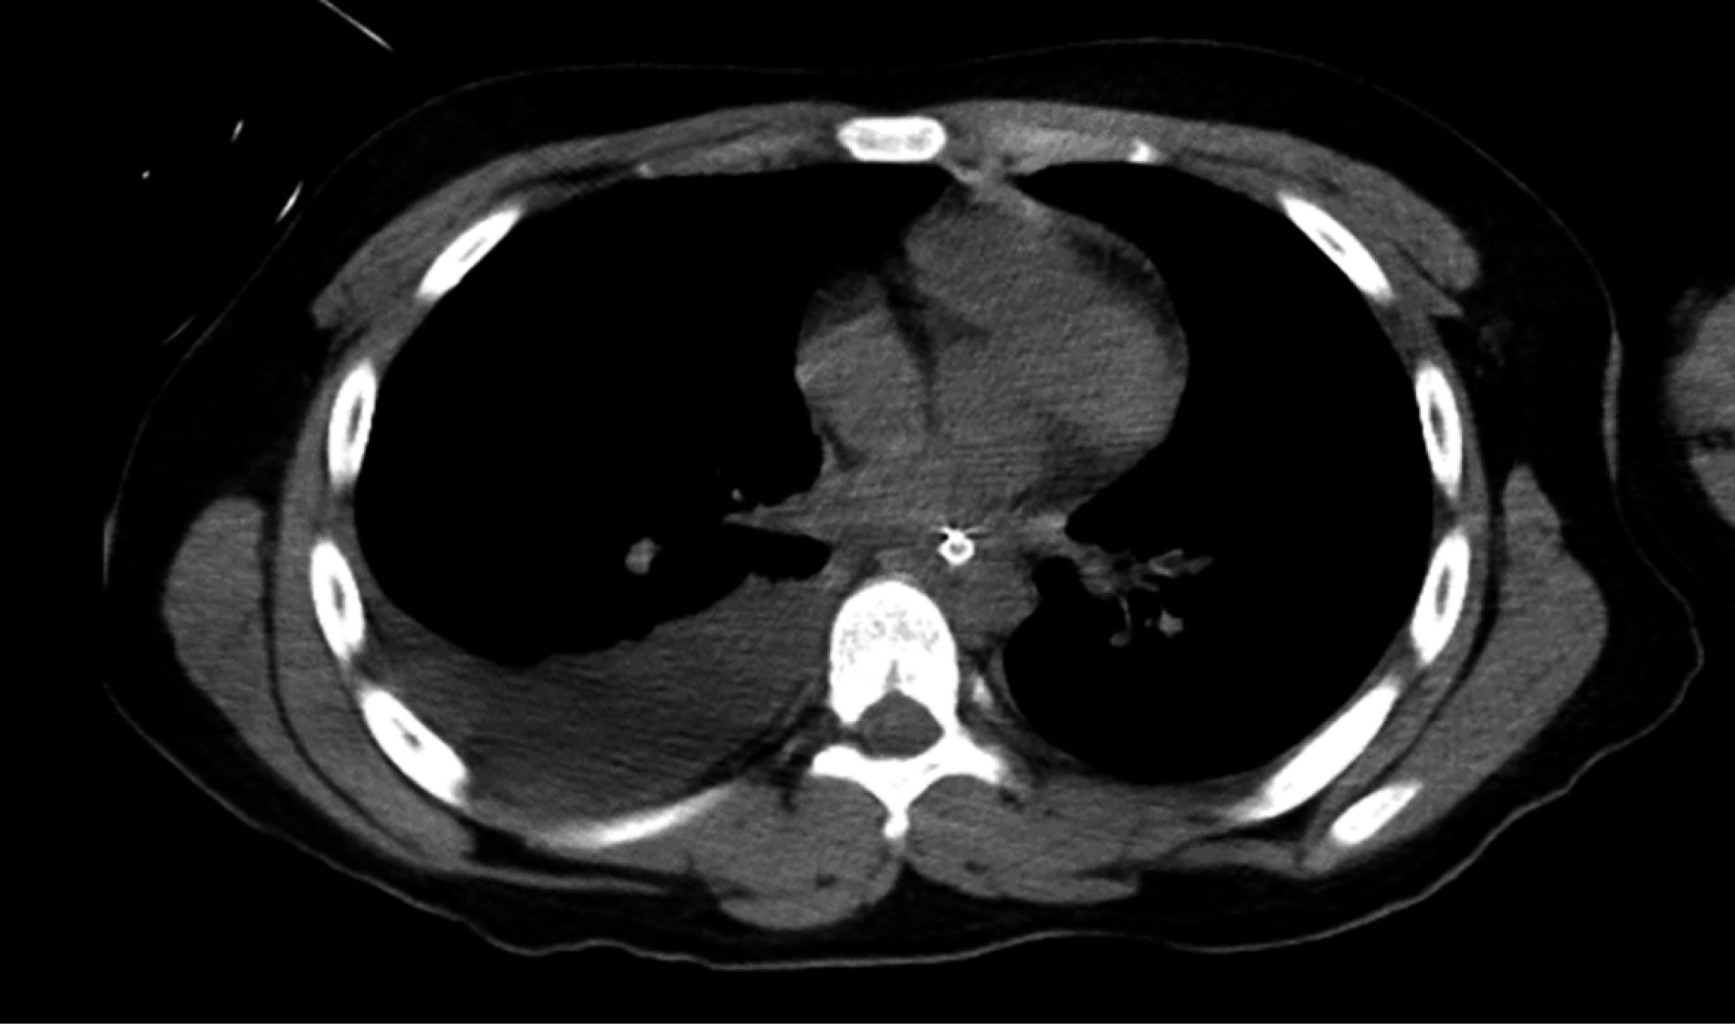

Tuvimos una defunción, correspondió a un varón de seis años, previamente sano, nueve días previos con cuadro gripal, dolor abdominal, vómito, fiebre no cuantificada. Posteriormente presentó hematemesis y epistaxis; al presentar alteración del estado de alerta acudió a nuestro hospital, ingresando con Glasgow de 10, dolor abdominal intenso. Sus resultados de laboratorio se expresan en la Tabla 5. En la tomografía pulmonar se aprecia derrame pleural (Figura 1) y en la tomografía craneal hemorragia subaracnoidea en región occipital (Figura 2). El paciente presentó paro cardiorrespiratorio, recibió maniobras de reanimación avanzada; sin embargo, falleció.

Figura 1